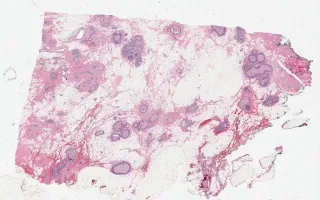

Breast, Ductal carcinoma in situ

Ductal carcinoma in situ

42 year-old female, right-breast lumpectomy for ductal carcinoma in-situ (DCIS). The slide is provided for comparison with the post-chemotherapy re-excision specimen (see Related Content).

This slide shows the lumpectomy for ductal carcinoma in-situ (DCIS) and is provided for comparison with the post-chemotherapy re-excision (see Related Content).

Chemotherapy related changes can be detected in neoplastic as well as non-neoplastic tissue. Following chemotherapy, there is some evidence that suggests that in situ carcinoma is relatively more resistant to chemotherapy compared to invasive carcinoma.